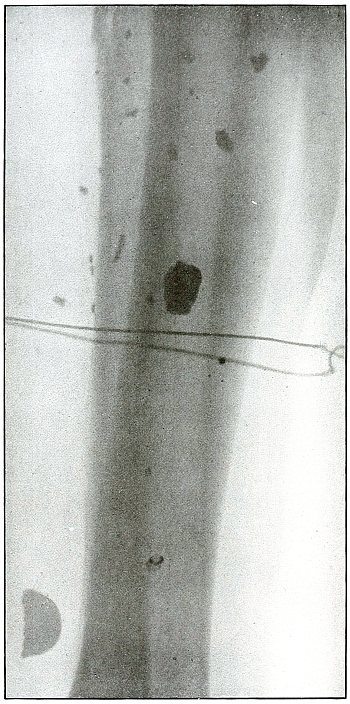

Rifle—Plate 7.

SPINAL REGION.

Gunshot Wound of the Spinal Region,

with Lodgment of the Missile.

The bullet was either dum-dummed or unjacketed because its soft nose

mushroomed, striking the crest of the ilium, penetrated the lumbar

muscles, and struck the side body of the third lumbar vertebra without

producing fracture.

The exposure, as the spinous processes show, was made with the spine

next to the plate, and the slight shadow, somewhat larger than the

projectile—to judge the size from the undeformed diameter—shows

it to be anterior to the vertebra. The shadow is deep enough to indicate

the location fairly near to the plate, and, almost certainly, not in

the abdominal cavity, where the distance from the plate would have

made the shadow less dense and the movement of respiration probably

would have given it a blurred outline. The shadow of the localizing

cross gives a standard of density to be compared with the shadow of

the projectile in making the estimation.

The treatment is conservative; only pain, paralysis, impaired

function, or sepsis indicate interference.